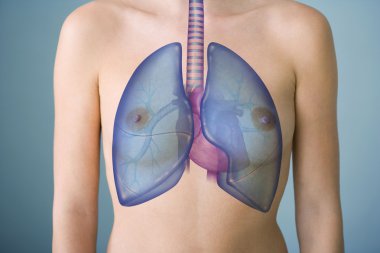

çizim, pulmoner dolaşım

ArkaplankişiİnsanKadınkanİlaçSolunumAvrupa DiliKardiyolojikalpdüzresim çalışmasıAkciğerSistemkemergemiüstünvenanatomiNormalauricletedavülarterAzalanyükselenCavaaortvena cavatorasikaşağıPulmonerventrikül20 30 yıldüz arka planKan damarıSolunum SistemiKan dolaşımıPnömolojiaortik kemerinen aortPulmoner dolaşımtorasik aortyükselen aortaPulmoner arterBenzer İçerikler